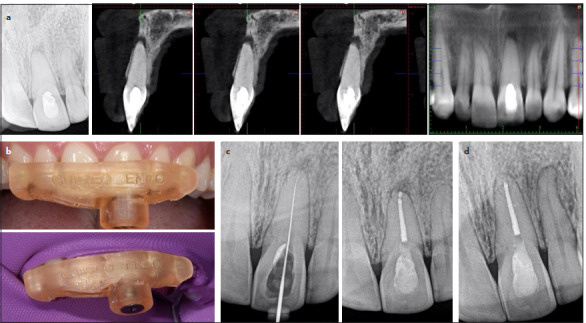

根管钙化是根管治疗的一大难题,可能导致治疗失败。困难在于进入、穿透和通过这些运河。本文报道了一系列的钙化根管成功治疗使用静态引导牙髓学。本文对11例钙化根管进行了静态引导根管治疗。样本包括四种牙齿类型,包括一个有两个管的前磨牙,使用两个模板(钻导)有效地管理。引导根管治疗是基于临床、放射学和锥束计算机断层扫描(CBCT)结果诊断的钙化根管的证据。采用高分辨率CBCT和口内扫描进行虚拟腔规划。CBCT和口内扫描叠加,虚拟滑套精确放置,以避免钻偏。制作并安装模板,低速钻孔引导入路,术中x线片监测。用k型锉平整运河,用Wave One Gold系统制备,2.5% NaOCl为灌溉剂。在所有情况下,虚拟规划的引导冠状和根管通道与3D打印模板相结合,可以通过封闭的牙髓空间进行根管定位,采用保守的进入方法,不会发生事故。这些病例表明,静态引导的牙髓治疗是一种安全准确的治疗方法,可以进入钙化管,减少工作时间,最大限度地减少牙齿结构的移除,降低医源性损伤的风险。(eej - 2024 - 07 - 106)。

Root canal calcification poses a substantial challenge in endodontic practice and may lead to treatment failure. The difficulty lies in accessing, penetrating, and negotiating these canals. This article reports on a series of calcified root canals successfully treated using static-guided endodontics. Eleven cases of calcified root canals were treated by the same endodontist using static-guided endodontics. The sample encompassed four tooth types including a premolar with two canals, effectively managed using two templates (drill guides). Guided endodontic treatment was based on evidence of calcified root canals diagnosed with clinical, radiographic, and cone beam computed tomography (CBCT) findings. A high-resolution CBCT and an intraoral scan were used for virtual cavity planning. The CBCT and intraoral scan were superimposed, and virtual sleeves were accurately placed to avoid drilling deviation. Templates were fabricated and fitted, and guided access was conducted with low-speed drilling, monitored with intraoperative radiographs. Canals were negotiated with K-files, and prepared with Wave One Gold system, using 2.5% NaOCl as irrigant. In all cases, virtually planned guided coronal and root canal access allied to the 3D printed templates allowed canal location through obliterated pulp spaces with a conservative access approach and without accidents. The cases demonstrated that static-guided endodontics is a safe accurate treatment approach to access calcified canals, reducing working time, minimizing removal of tooth structure, and decreasing the risk of iatrogenic damage. (EEJ-2024-07-106).